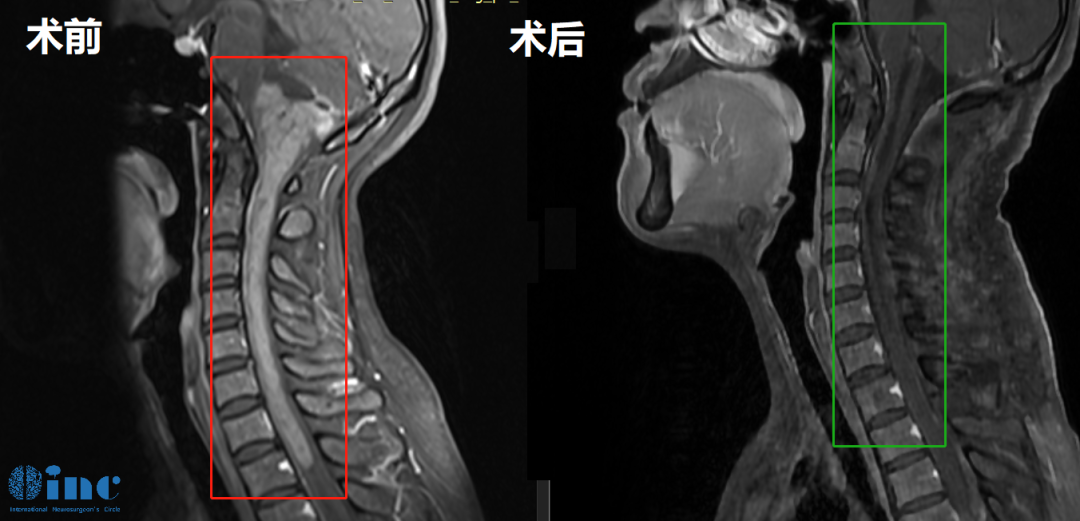

郑女士,33岁,2016年发现颈椎椎管内占位性病变,室管膜瘤可能性大。当时医生认为手术风险过高、可能导致瘫痪,未予进一步处理。2018年郑女士怀孕,孕晚期出现双下肢轻微麻木,出于对胎儿安全的考量,整个孕期均未接受任何治疗。2022年复查时,病变范围较2016年已显著扩大。

进一步检查显示,肿瘤起源于脑干,累及延髓和颅颈交界区,向下延伸贯穿整段颈部脊髓,直抵第一胸椎水平,病变纵向累及范围接近15厘米。病灶位于生命中枢,手术造成瘫痪、呼吸心跳骤停、昏迷乃至植物人状态的风险极大。

巴教授对影像资料的评估直接而清醒:"影像显示这是一例累及范围极广的髓内肿瘤,起源于脑干下部,受累区域包括延髓和颅颈交界区,并向下延伸至整个颈段脊髓及第一胸椎水平。我此前曾成功为类似的巨大肿瘤患者实施手术,但必须说明,这种范围的切除手术极其耗力耗时,相当于同时完成两台独立的手术——不仅是肿瘤切除本身需要大量时间,还需同期完成从颈1到胸1水平的广泛椎板成形术及枕下开颅术。患者本应在肿瘤尚小的时候就接受手术,现在的手术是必要的,也是可行的。"

这个案例说明:当肿瘤持续生长、神经功能进行性受损时,选择"尽快手术"是阻止更坏结果发生的必要举措。最终,巴教授在苏州大学附属第四医院为郑女士顺利完成了手术。